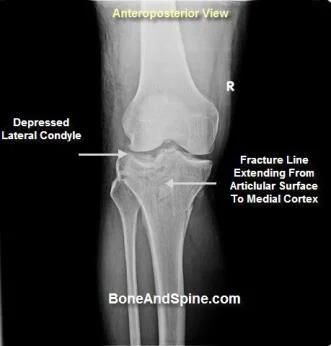

- According to fracture pattern:

-

Compressed

Depressed